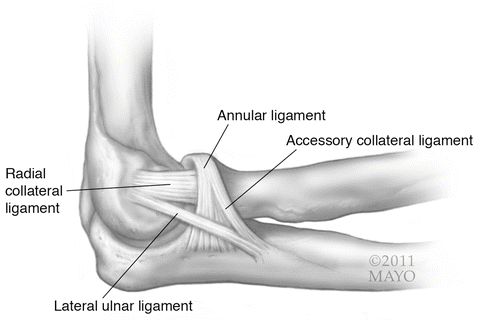

What is the humeroradial/humeroulnar joint?

The elbow joint.

What is the joint shown here? (Be specific, list both names).

The humeroradial/humeroulnar joint.

Find the radial collateral ligament.

(See bolded text in image).

Find the ulnar collateral ligament.

(See bolded text in image).

What is the name of the superior and anterior (top-right) ligament?

Annular ligament.